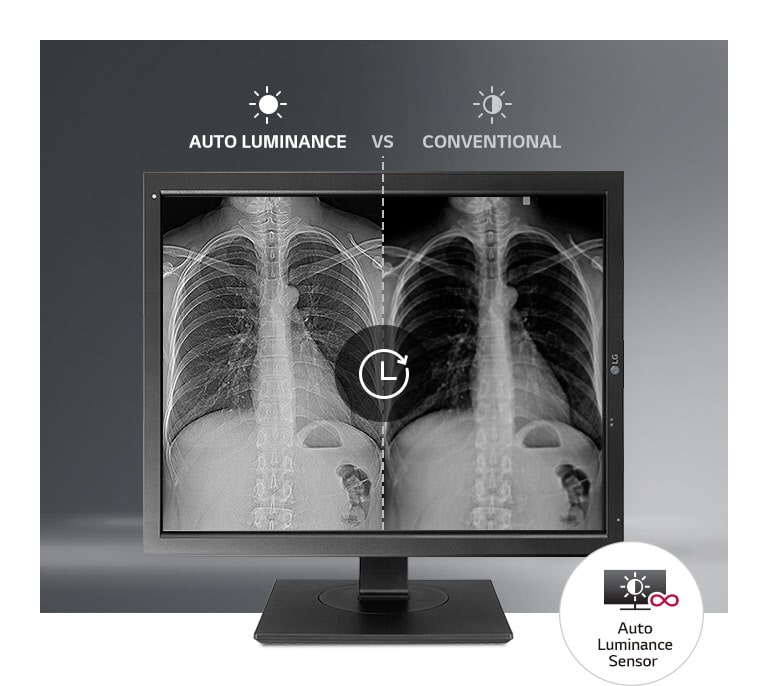

Productive, Efficient Work

*Image for illustration purpose only.